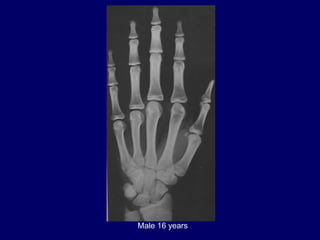

Male 16 years